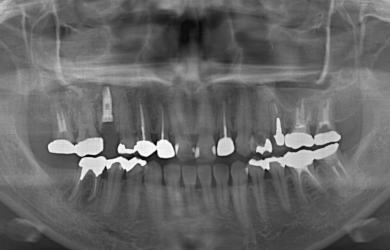

抜歯即日スピードインプラント+ソケットリフト

| 治療方針 | 初期固定に必要な骨の量がほとんどないため、ソケットリフト法を併用した抜歯即日スピードインプラントを行ってみるが、初期固定がとれなかった場合には通常の段階的な方法にてまず抜歯を行い、その後4カ月ほど待ち、骨が出来てからインプラント手術を行う。 | ||||||||||||||||||||||||||||||||

| 治療内容 | インプラント1本(抜歯即日スピードインプラント+ソケットリフト)、ハイブリッドセラミック1本、メタルボンドセラミック2本、ハイブリッドセラミックインレー1本 | ||||||||||||||||||||||||||||||||

| 治療期間 | 7ヶ月 |